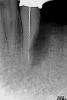

x3m Опубликовано 10 сентября, 2013 Автор Поделиться Опубликовано 10 сентября, 2013 (изменено) чуда, к сожалению, не произошло. сегодня посещение (по поводу расцементировки временного мостовидного протеза 11-23) показало следующую картину в 3 сегменте: обильное гнойно-кровянистое отделяемое (у края десны), грануляционная ткань. у клыка подвижность 2 ст., у имплантата - 3 ст. РВГ: Что видите вокруг имплантата? П.С. Кто знает, каков алгоритм действий в этой ситуации, когда автор-имплантолог находится в Швейцарии?(протоколирование диагностики, манипуляций, подтверждение показаний к удалению и т.д.?) Изменено 10 сентября, 2013 пользователем x3m Ссылка на комментарий

x3m Опубликовано 15 сентября, 2013 Автор Поделиться Опубликовано 15 сентября, 2013 Большое спасибо, Олег Юрьевич, за мнение! Докладываю обстановку: Позавчера удалили имплантат 3.4.Об-но: подвижность уже даже не 3 степени, гной, грануляции, зондирование парозондом = 12мм вглубь.После удаления опр-ся костный дефект, зондируется дефект корня 3.3.рвг: похоже, пересекается к/канал и дефект корня дистально (смотрели в разных проекциях). Но... Удалять сразу 3.3 не стали, завтра проведем диагностическое депульпирование + конденсацию кальцийсодержащего рентгенконтрастного материала с целью выявления соустья канала с дефектом корня (не продавится ли?).По результату отпишусь. 3 Ссылка на комментарий

x3m Опубликовано 18 сентября, 2013 Автор Поделиться Опубликовано 18 сентября, 2013 (изменено) протоколирование перед удалением:Алле- -АП! "Удалить за 0,60 сек.": - только что из лунки. на поверхности гной, ошметки кости и чуть свежей крови - видимо, не прижился ... кюретаж, губка в лунку, диплен сверху: ...и рентгенконтроль:смутило наложение тени на пульповую камеру (хочется, чтобы это была костная тень, а не дефект корня с перфорацией). Через 3 дня:подтверждение перфорации (инструменты не цепляют по дистальной стенке, ашка не уперлась ни во что и проскочила почти до апекса): При конденсации кальций тоже не вышел за канал (уф, полегчало): пока 3.3 решили не удалять, наблюдаем. Вопрос по клыку:какой прогноз и какие действия? да, меня вот еще что "несколько смущает" в 4 сегменте:состояние имплантатов в позиции 4.5, 4.6 после установки (апрель с.г.):вид сейчас: МК, шатающийся Clip F в шахте, обратный угол коронок с поднутрением (на фото - зондируем резьбу), там налет и легко кровоточит, язычно над десной - полированная шейка имплантата.а на КТ имплантат 45 в кости на 4мм вестибулярно...как это может работать в долгосрочном прогнозе??? Изменено 18 сентября, 2013 пользователем x3m Ссылка на комментарий